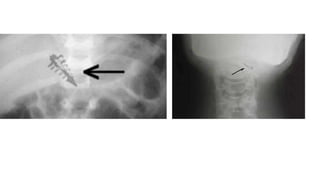

A partir dos anos 1960, começaram

a aparecer pessoas com estranhas

marcas no corpo: cicatrizes,

pequenas cavidades, cortes por laser

em série.

São o resultado de cirurgias,

desinfecção, retirada de fluidos,

inserção de microchips...

IMPLANTES ALIENÍGENAS

mais de 50 milhões de IMPLANTES ALIENÍGENAS em todo o mundo

Implantes são microchips que servem para:

- Rastreamento/monitoramento

- Controle mental

- Aperfeiçoamento genético/energético

Marcas nos abduzidos Apartir dos anos 1960, começaram a aparecer pessoas com estranhas marcas no corpo: cicatrizes, pequenas cavidades, cortes por laser em série. Tornozelo, pulso, costas, quadris, seios etc. São o resultado de cirurgias, desinfecção, retirada de fluidos, inserção de microchips...

mais de 50milhões de IMPLANTES ALIENÍGENAS em todo o mundo Implantes são microchips que servem para: - Rastreamento/monitoramento - Controle mental - Aperfeiçoamento genético/energético

Este tipo deimplante é encontrado em inúmeros abduzidos